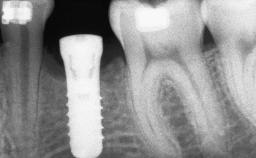

A woman in her mid-fifties was referred by a dental student for dental implant placement. Both posterior segments of the mandible had been edentulous for more than 4 years, the only residual tooth being the right lower first premolar. The patient had used a removable partial denture but was not entirely satisfied with its function. The clinical examination revealed a sharp edentulous ridge in both posterior segments of the mandible, and the patient was told that it would not be possible to insert implants into this thin edentulous ridge without significant augmentation of the alveolar ridge. Her medical history revealed no significant findings and no underlying disease that might have complicated surgical procedures. During the presurgical examination, the patient reported that she was a little apprehensive about bone grafting. After being informed about the surgical procedures and potential postoperative complications, she accepted the proposed surgical plan of bone grafting and subsequent placement of implants.